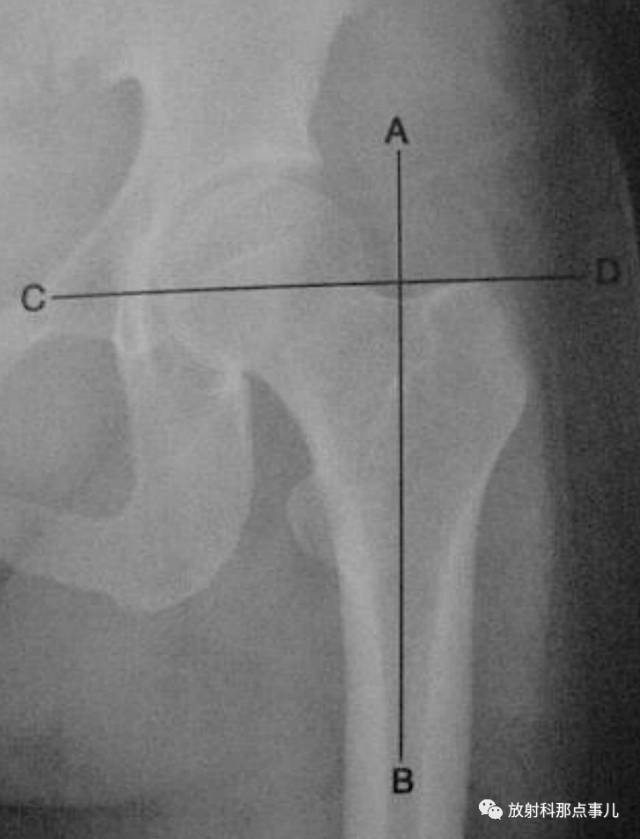

Skinner线

在成人髋关节正位片上,从股骨大转子顶端作股骨纵轴线AB的垂线CD,正常情况下,此线应通过圆韧带窝或其下方,圆韧带窝至上述两线交点的距离是4~5cm。若Skinner线超过圆韧带窝,提示股骨颈或大转子错位骨折。